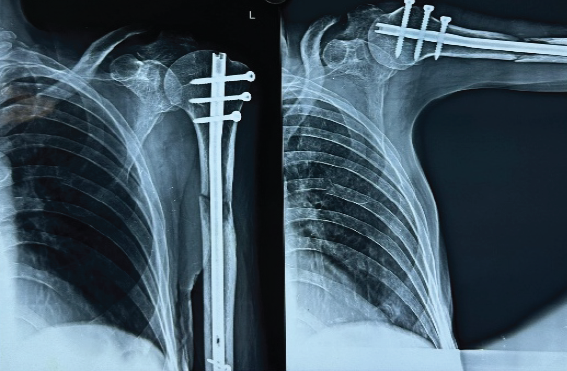

Plain radiograph of the left arm showed lytic lesion of the proximal shaft humerus (Fig. 5). Skeletal survey of the patient revealed multiple lytic lesions over the skull characteristic for multiple myeloma (MM). On further workup, Myeloma profile revealed a serum Calcium – of 7.7 mg/dL, serum beta-2 microglobulin – above 20,000 ng/mL, M band on serum protein electrophoresis.

Figure 5 : Plain radiograph of the left arm showing lytic lesion of the proximal shaft of humerus (89-year-old male with multiple myeloma). Skeletal survey revealed multiple lytic lesions over the skull characteristic of multiple myeloma involvement. The proximal humeral shaft location is the second most common site for long bone metastases and pathological fractures.

Intervention

Patient was managed with closed reduction and internal fixation using IM humerus nailing (Fig. 6) along with biopsy.

Figure 6 : Postoperative radiograph of the left humerus following closed reduction and internal fixation using intramedullary humerus nailing. The intramedullary nail provides stable fixation through the lytic lesion, allowing early mobilization and rehabilitation despite the patient’s advanced age (89 years) and systemic disease burden.